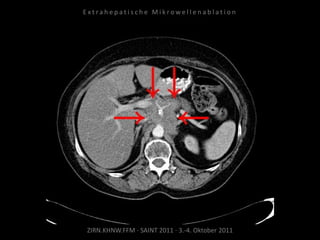

Bildgebung vor MWA:

CT vom 14.07.2010

Metastase lateral der linken Niere

nahe Colon descendens progredient.

Situation:

Metastasierung über längeren Zeitraum

lokal begrenzt,

1 Metastase progredient.

Organnahe Lage in unmittelbarer

Nachbarschaft zur linken Niere bzw. zum

Colon descendens.